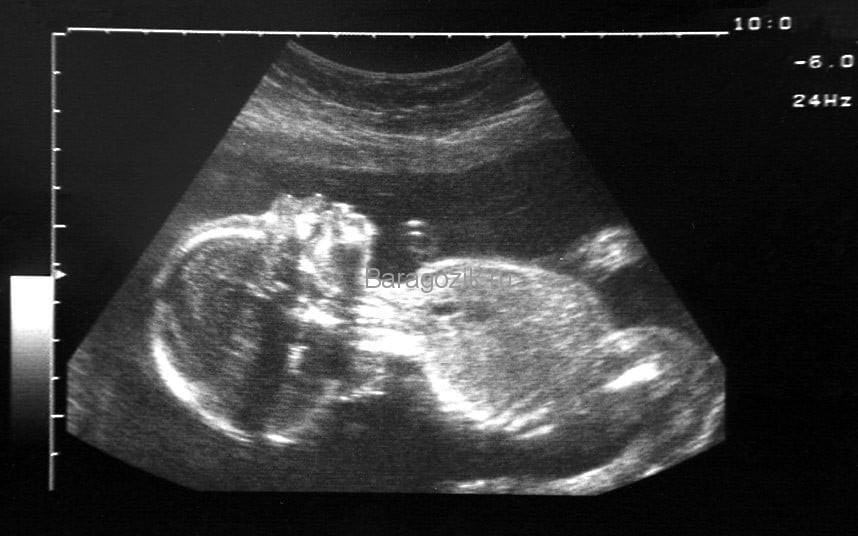

Что видно на УЗИ?

На этой неделе УЗИ считается необязательным, его назначают только в случае необходимости.

При проведении исследования большое внимание уделяется состоянию плаценты, поскольку от ее показателей зависит то, как пройдут роды. Толщина ее стенок должна равняться 24 см. С каждой неделей толщина увеличивается приблизительно на 1 см.

На мониторе мама сможет увидеть своего малыша в позе эмбриона. Его ручки скрещены на груди, ножки также скрещены и прижаты к животику, а головка опущена к груди.

Что касается УЗИ на 24-й неделе беременности, то на этом сроке его обычно не нужно делать. Но если ранее будущая мама не проходило данное исследование, то пора этим заняться. На этом сроке с помощью УЗИ измеряют размеры ребёнка: окружность головы, живота, ножек, ручек и прочее. Это нужно для того чтобы понять, соответствуют ли размеры малыша оптимальным размерам плода на данном сроке. Кроме того, на УЗИ тщательно исследуются внутренние органы ребёнка с тем чтобы выявить возможные пороки в их развитии. Околоплодные воды также исследуются. По их состоянию можно понять, нормально ли развивается беременность. По состоянию плаценты определяют уровень кровоснабжения и питания плода.